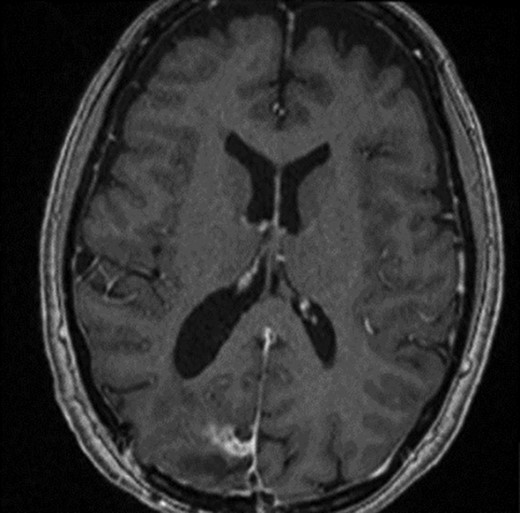

The operation was successful with a post-operative MRI within 48 h demonstrating complete resection of the tumour and resolution of the cystic lesions, but persisting intraparenchymal oedema (Fig. 3). The patient had an uncomplicated two-day stay in a neurosurgery high dependency unit postoperatively before being stepped down to the general neurosurgery ward. She was reviewed by the microbiology team and worked up for the source of infection. Blood cultures, urine cultures, CXR and transthoracic echocardiography were all negative for a source of infection. Intra-operative pus cultures isolated MSSA. The histopathology of the tumour was Meningioma WHO Grade 1 with large areas of necrosis and secondary abscess formation. She was discharged feeling well 5 days later after a satisfactory biochemical and clinical response. She was given a weaning course of steroids and a 6-week course of intravenous ceftriaxone via a PICC line as an outpatient as per microbiology advice. Ophthalmology assessment 3 months after discharge confirmed a left inferior quadrantonopia and preserved visual acuity. Repeat MRI and clinic review 8 weeks later showed no radiological residual tumour or oedema (Fig. 4), and the patient’s limb function recovered completely but had ongoing visual symptoms.

T1 weighted axial MRI postgadolinium enhancement within 48 h post-operatively. Small amount of enhancement within the surgical bed remains. Good resection margins with vasogenic oedema. This may represent a small residual. The rim-enhancing cystic lesions appear to have resolved.